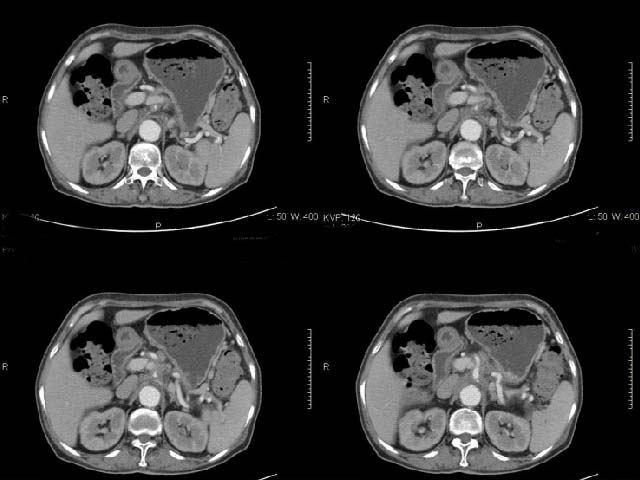

女,69岁,浑身乏力,腹泻半年余,无腹疼,排泄物中含有脂肪球,抗炎治疗一周仍不缓解,来我院检查发现明显低钾血症,给予补钾(氯化钾)一周后,血钾恢复正常,经化验检查,尿钾持续明显高于正常,临床考虑患者不仅消化道失钾,还伴有泌尿系统失钾,故进行ct增强检查看肾上腺是否有病变。ct表现为胰腺肥大,而且体尾部强化较弱,明显呈稍低密度,胰尾见有更低密度,而且胰腺与周围组织的脂肪间隙不清,大血管周围似乎有包绕现象,患者是否有过胰腺炎病史,家属说不清楚;而双侧肾上腺大小形态,本人认为未见异常,本人倾向于考虑:慢性胰腺炎伴假性囊肿,不排除胰腺占位可能;但是不知怎么解释持续尿钾现象。请大家发表高见!

静脉期